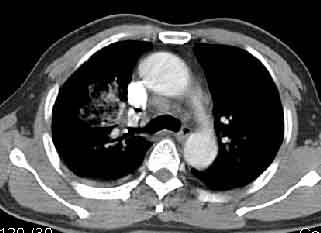

该病例我的诊断意见:右肺上叶周围型肺癌伴纵隔和右肺门淋巴结增大和右肺上叶阻塞性肺炎{病灶周围致密影以近肺门侧明显!}。右侧少量胸腔积液。

一. 1)症状有无发热及慢性过程.2)化验室检查?3)有无tb接触史?二.右肺上叶见片团状影,边界欠清,外侧方见一结节状软组织影,密度欠均匀,内可见低密度坏死区.周围强化明显,肺内见纤维索条影,局部胸膜增厚,但无明确胸膜凹陷.上叶支气管壁增厚,肺门及纵隔淋巴结增大.右侧胸腔少量积液.诊断意见:1右肺上叶慢性感染性疾病(肺tb?)伴肺门,纵隔淋巴结大.右胸少量积液.右肺上叶结节影多为tb球?2右肺上叶周围型肺ca伴肺门,纵隔淋巴结转移待排.右肺上叶炎变(肺门及纵隔淋巴结压迫).右胸少量积液.等待随返结果.

右上肺周围性肺癌,阻塞性肺炎考虑为肿大淋巴结压迫上叶支气管引起。